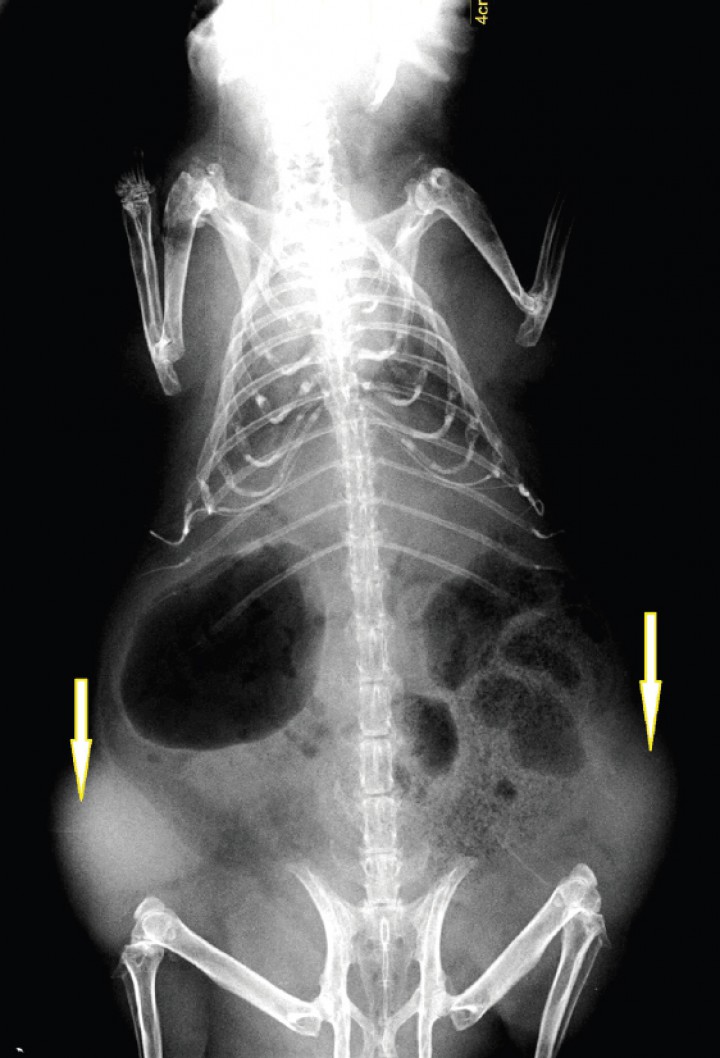

Durante la exploración física se evidencia una alopecia bilateral en los flancos, sin eritema ni descamación (Fig. 5). Tampoco hay cambios de coloración de la piel, pero se detecta la presencia de dos masas palpables a ambos lados del abdomen caudal, de consistencia bastante sólida. Se decide realizar una exploración ecográfica en la que se evidencian dos masas de ecogenicidad mixta, sin presencia de líquido, descartando además, por la situación anatómica, que se trate de quistes ováricos. Se sospecha que las masas son extraabdominales y se realiza una radiografía donde se constata que ambas son subcutáneas, quedando confirmado que no sean quistes o tumores de origen ovárico (Fig. 6).

<p>Proyección ventrodorsal del caso nº 2. Se observan dos masas de opacidad tejido blando (flechas) localizadas en el subcutáneo.</p>

Figura 6

Proyección ventrodorsal del caso nº 2. Se observan dos masas de opacidad tejido blando (flechas) localizadas en el subcutáneo.